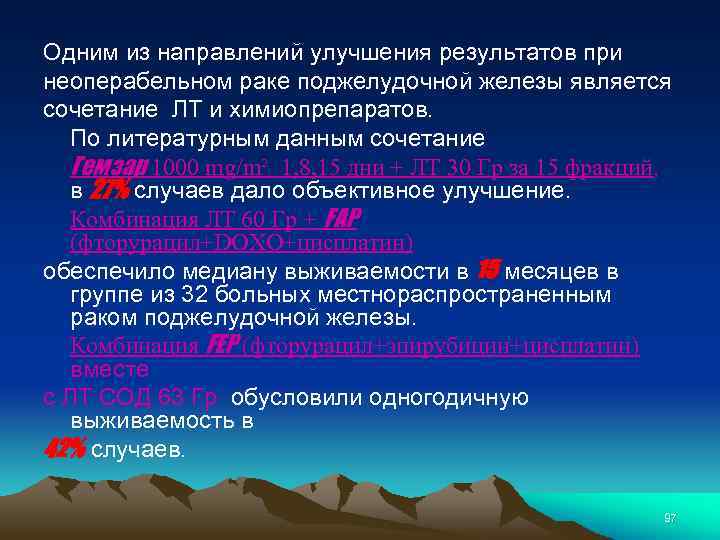

Одним из направлений улучшения результатов при неоперабельном раке поджелудочной железы является сочетание ЛТ и химиопрепаратов. По литературным данным сочетание Гемзар 1000 mg/m² 1, 8, 15 дни + ЛТ 30 Гр за 15 фракций, в 27% случаев дало объективное улучшение. Комбинация ЛТ 60 Гр + FAP (фторурацил+DOXO+цисплатин) обеспечило медиану выживаемости в 15 месяцев в группе из 32 больных местнораспространенным раком поджелудочной железы. Комбинация FEP (фторурацил+эпирубицин+цисплатин) вместе с ЛТ СОД 63 Гр обусловили одногодичную выживаемость в 42% случаев. 97